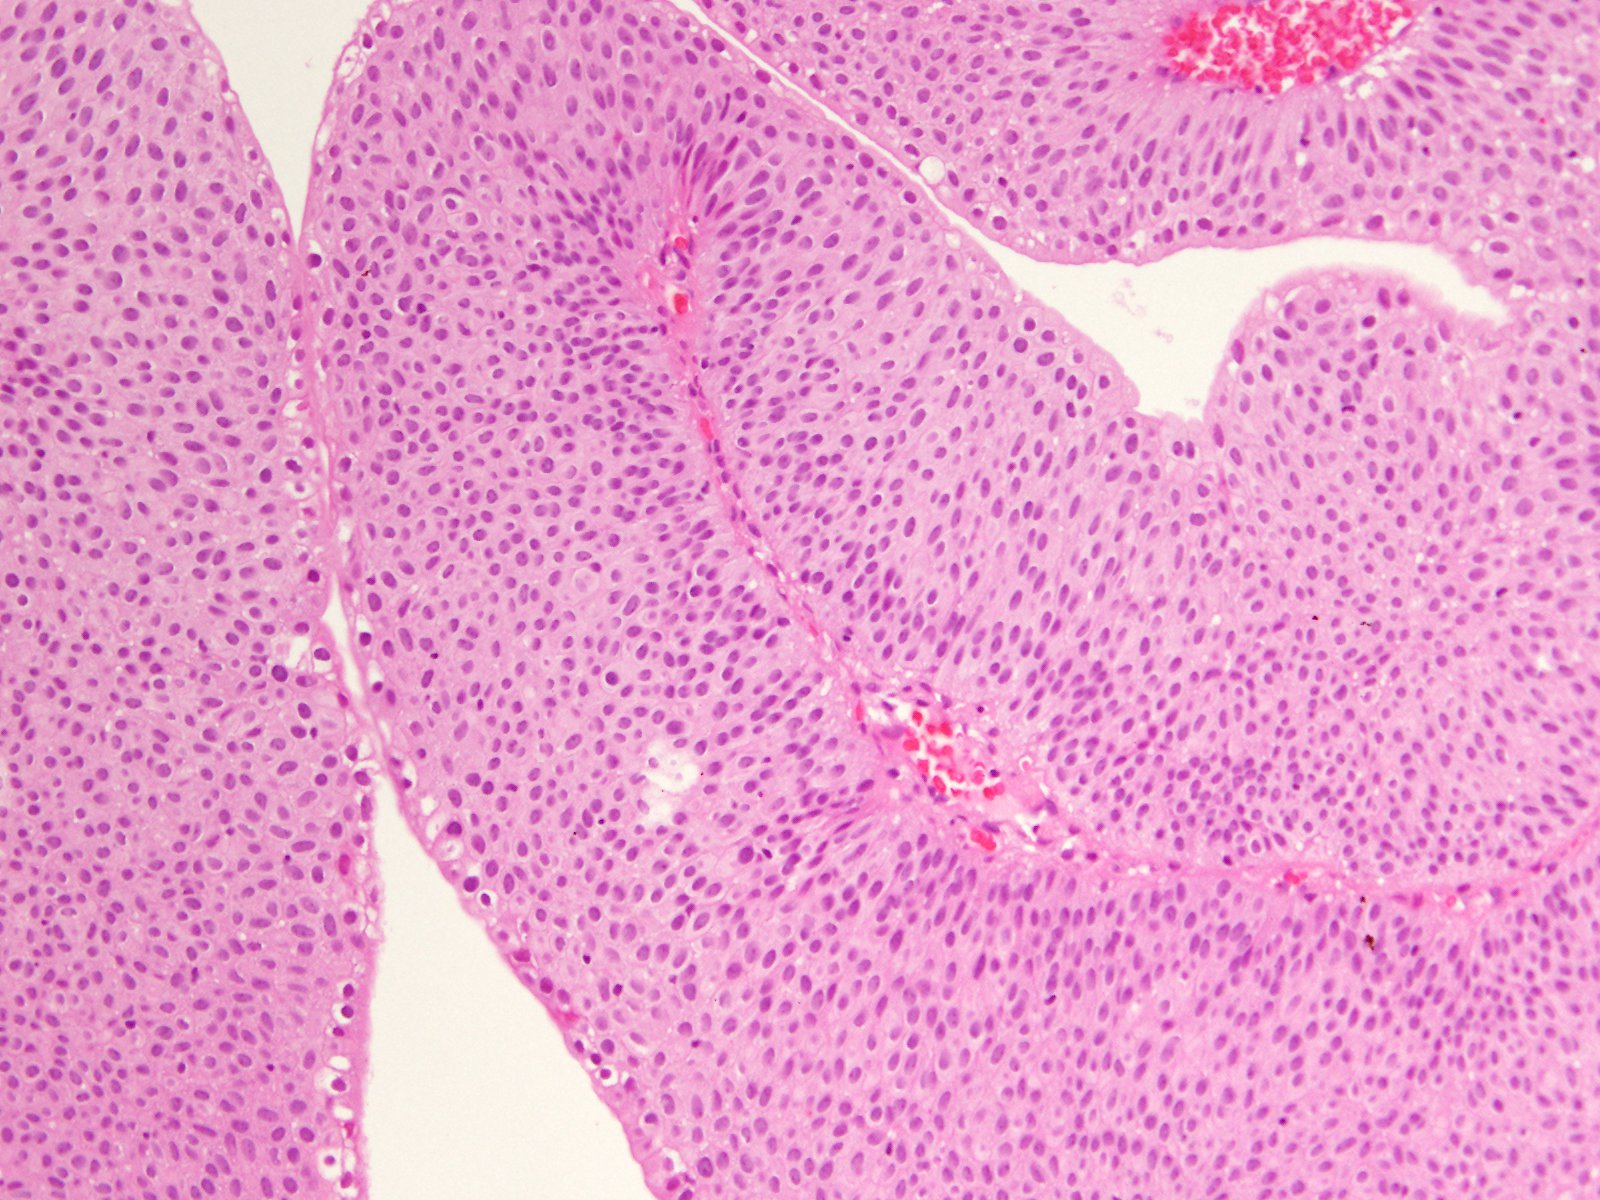

Consensus grade: Low-grade papillary urothelial carcinoma (LG-PUC)

would call it LG, but PUNLMP is an option. I thought there are too many layers to call it PUNLMP |

borderline between PUNLMP and LGPUC |

Case description (by case creator):

71 y/o, bladder tumor.